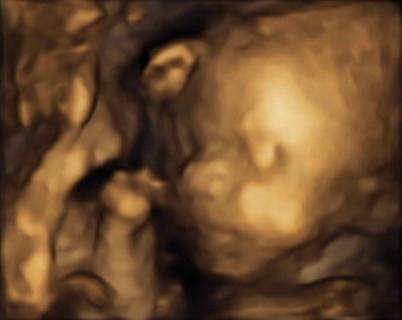

Zobacz załącznik 555316Zobacz załącznik 555317

No więc jest dwóch chłopów na 100% i to jaki kawał chłopów! Obaj srednio po 1111g gdzie na tym etapie powinno byc z 900ja nie wiem jak ja ten brzuch udzwigne jak będą rosnąć w takim tempie